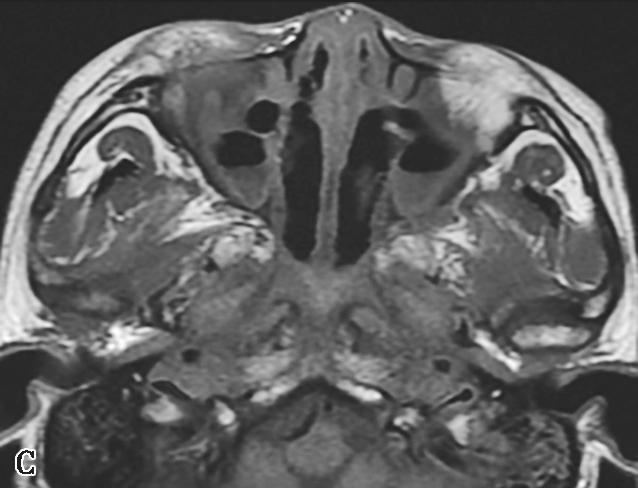

图1-3-23 急性侵袭性真菌性鼻窦炎

A、B.横断面、冠状面CT骨窗,示双侧蝶窦、后组筛窦软组织影,密度不均,窦壁骨质硬化伴局部骨质破坏,累及双侧圆孔、翼管;C~E.MRI横断面T 1 WI、T 2 WI、T 1 WI+FS+C,示双侧蝶窦、后组筛窦内混杂长T 1 、长T 2 信号,窦腔内见斑片状短T 1 、短T 2 信号影,增强扫描边缘强化,前颅底脑膜增厚强化